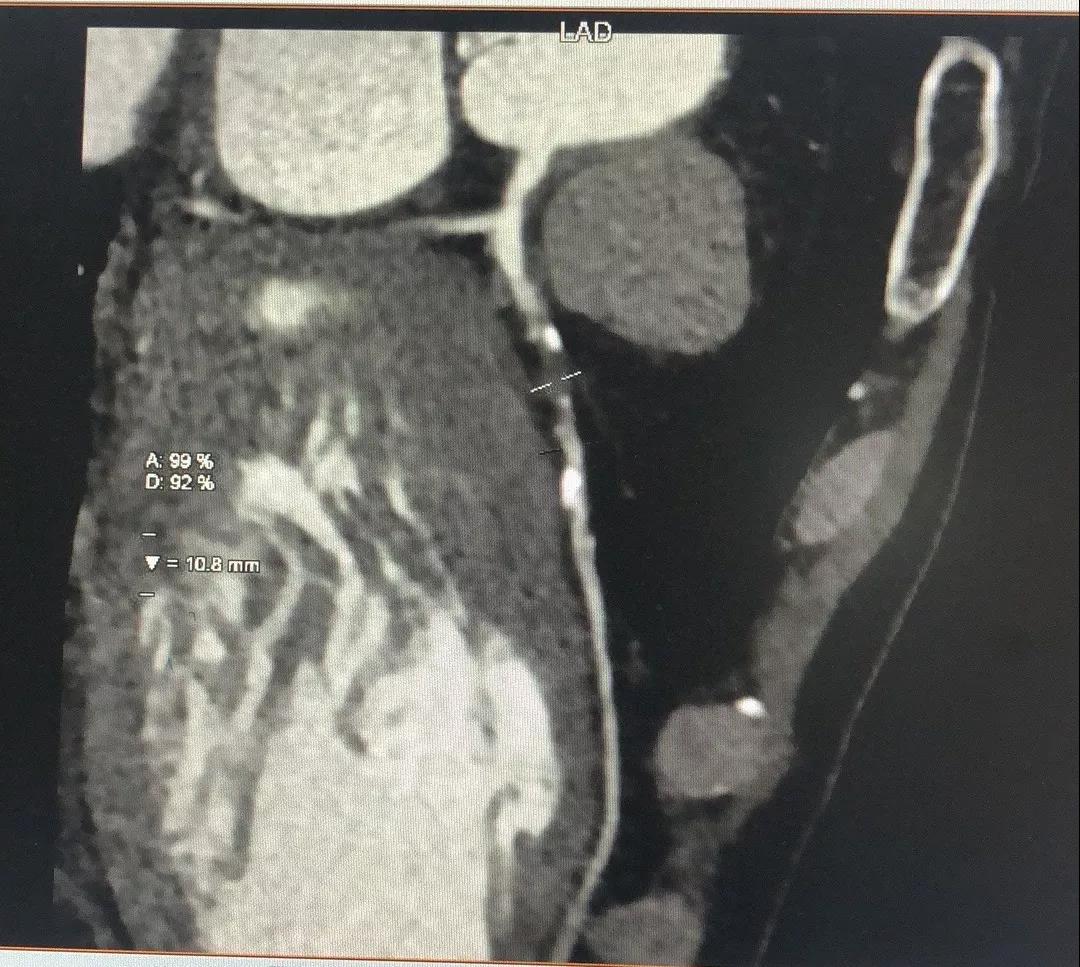

关于LCX

LCX CTA特点:

1、LCX血管相对比较“健康”;

2、LCX近中段发出比较粗大的侧枝逆向供应右冠左室后支,侧枝血管仅轻度扭曲;

3、LM前分叉相对“健康”。

有了上述信息,结合冠脉造影资料,逆向开通RCA就有了一根条件相对比较好的侧枝血管。